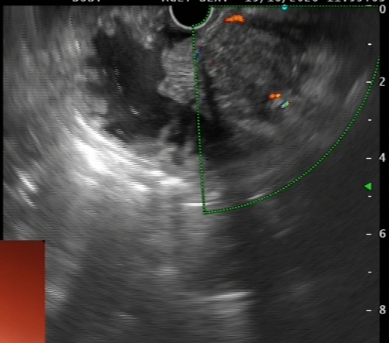

⑦超声胃镜

EUS是将微型高频超声探头安置在内镜前端,在内镜直视观察腔内形态的同时,又可进行实时超声扫描近距离探查,使靶器官的结构与图像更为清楚,为临床治疗方案的选择提供了有力的支持。我院消化内镜于2004年在四川省率先开展EUS新技术,目前拥有国内最新—代的EUS系统,它集超声内镜主机、高频小探头、三维超声探头、环扫内镜超声等 先进设备为—体。我院EUS诊疗组,现有教授1名、副教授2名,每年完成近千例消化道EUS诊疗,EUS诊疗技术达到省内先进水平。

为什么需要EUS

普通内镜检查只能发现消化道表面的病灶,通过EUS显示消化管壁层次结构及周围脏器病变,能更准确判断胃肠隆起病变的 性质、来源、肿瘤的浸润深度,还能取活检,指导确定治疗方案及判断疗效。

EUS适应症

1、消化道肿瘤的诊断,术前分期、术后随访

2、判断粘膜下肿瘤的起源与性质

3、胰腺与胆道疾病的诊断与鉴别

4、食管胃底静脉曲张的诊断与疗效判断

5、溃疡性病变良恶性的判断

6、各种需要EUS介入治疗的疾病